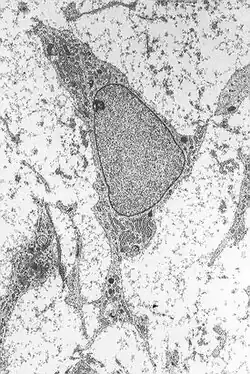

Célula mesenquimatosa

As células mesenquimatosas são células-tronco adultas, pertencentes ao mesênquima, um tecido embrionário. Também estão presentes na pessoa adulta, mas à medida que ele vai envelhecendo, a quantidade destas células no organismo vai diminuindo

Ela se diferencia em muitos tipos diferentes de células, como os fibroblastos, osteoblastos, condrócitos, leucócitos e o mastócito. São importantes na regeneração do tecido.[1][2][3][4]